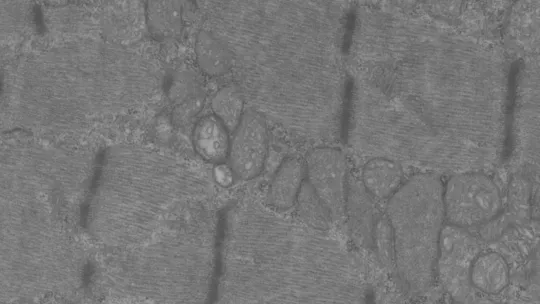

El artículo describe el fenotipo animal y explica que la eliminación de Opa1 únicamente en la fibra muscular del músculo esquelético, acaba generando un proceso inflamatorio agudo que se transfiere de la fibra muscular a todo el organismo. La respuesta inflamatoria paraliza el crecimiento y tiene un impacto en la longevidad del animal. Los científicos detallan también los actores moleculares principales en la vía de señalización celular a través de la cual se activa la respuesta inflamatoria en el músculo.

Opa1 es una proteína de fusión mitocondrial. Su función es fusionar las membranas internas de las mitocondrias. De mitocondrias hay en todas las células y tejidos (a excepción de los glóbulos rojos) pero son especialmente abundantes en músculos e hígado, y su principal función es convertir el alimento en energía. Las mitocondrias son muy dinámicas, se juntan y separan, se expanden y encogen constantemente. A estas procesos se les conoce como dinámica mitocondrial.